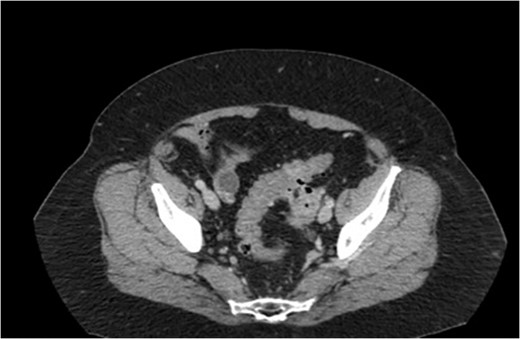

Two weeks later the patient was taken to the operating room for a hand-assisted laparoscopic colon resection and left oophorectomy. Intraoperatively, there were adhesions between the sigmoid colon and left anterolateral pelvic sidewall. Figure 3 shows the inflamed left ovary and fallopian tube adjacent to the sigmoid colon. The left ovary and a small portion of the left fallopian tube were dissected, and then resected en bloc with the sigmoid colon. Figure 4 depicts the uterus status post-resection. An end-to-end anastomosis was performed to the inraperitoneal rectum. The patient had an uncomplicated hospital course and was discharged home on post-operative Day number 2. One month later, the patient was doing well with normal bowel function, resolution of her UTI’s and resolved abdominal pain.

Intra-operative findings of the colo-ovarian fistula including grossly inflamed left ovary and fallopian tube.